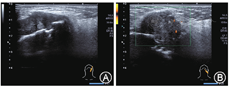

患者女,46岁,8年前发现左侧颌下区肿物,偶有疼痛,缓慢增大。入院查体:患者颌面部不对称,左侧腮腺咬肌区肿胀,左侧颌下区可触及一大小约3.0 cm×2.0 cm肿物,触之疼痛,质中等。常规超声所见:包绕左侧下颌支可见一不均质低回声肿物,大小4.3 cm×3.2 cm×3.4 cm,形态不规则,未见包膜,内可见点状血流信号,局部破坏下颌骨。颌下未探及正常颌下腺组织。超声提示:包绕左侧下颌支肿物,考虑颌下腺癌(如图1)。CT平扫提示:左侧下颌骨旁占位,侵犯下颌骨。术前细针穿刺病理提示:多形性腺瘤。术前患者以"左侧颌下腺多形性腺瘤"为诊断行左侧颌下腺及左侧咬肌区病损切除术伴下颌骨部分切除术。术后病理提示:涎腺腺样囊性癌。术后更正诊断为"左侧颌下腺腺样囊性癌"。